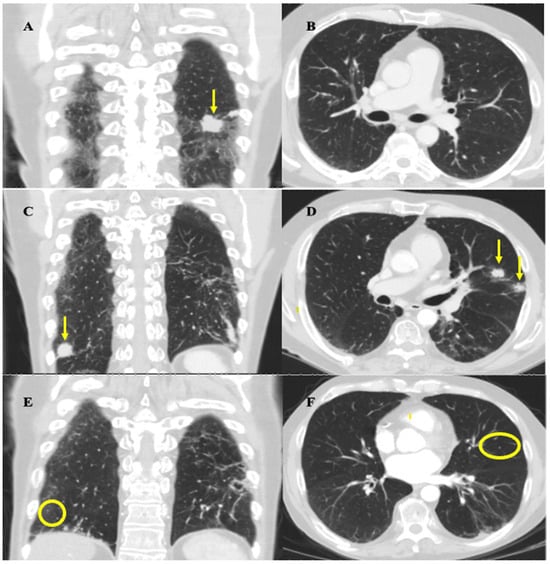

In the summer of 2019, a 58-year-old male patient presented to a walk-in clinic in London, Ontario, Canada for investigation of a 1.5 cm-by-2.5 cm, painless, left-sided neck mass. A CT thorax scan in September 2019 showed a large mass located posteriorly at the left lung base measuring 2.8 × 3.4 cm in size along with multiple other smaller pulmonary nodules ranging from 5 to 15 mm, present in the left base, left upper lobe, right middle lobe, and right hilar and pre-carinal regions, highly suspicious for metastatic disease (Figure 1A,B). The pathology obtained via fine needle aspiration (FNA) of the neck mass was consistent with metastatic SCLC. Staging workup included a magnetic resonance imaging (MRI) head scan, which showed no intracranial metastases, and a positron emission topography (PET) scan. This scan showed increased uptake in the largest lung mass as well as multiple right and left-sided pulmonary nodules ranging from 0.7 to 1.7 cm in size, and in the neck mass plus multiple left-sided cervical lymph nodes ranging from 0.5 to 0.9 cm in size (Figure 1C,D). These results confirmed the diagnosis of ES-SCLC.

Figure 1.

CT thorax and 18-Fluorodeoxyglucose (FDG)-PET scans at initial diagnosis. Yellow arrows depict radiological findings. (A) Coronal image from the CT thorax scan showing the largest mass in the left posterior lung base, measuring 2.8 × 3.4 cm in size. (B) Axial image from the CT thorax scan showing an additional view of the metastatic nodules in the posterior left lung. (C) Coronal images of the thorax on the FDG-PET scan show the largest FDG-avid lung mass, in the left posterior lung, and the adjacent hypermetabolic nodule. (D) Coronal images of the head and neck on the FDG-PET scan show a left-sided nodal conglomerate in the neck measuring 3.4 × 4.3 × 6.5 cm along with adjacent hypermetabolic lymph nodes measuring 0.5–0.9 cm (not well demarcated in image).

Coronal and axial mid-lung CT thorax images highlighting important stages of disease progression and response to therapy. Images were obtained at approximately the same slices for each time point. (A,B) February 2020 imaging after induction chemotherapy and radiation showing treatment response. (A) Arrow highlights reduction in size of largest left lung nodule from 3.4 × 2.8 cm to 2.7 cm × 1.6 cm. (B) No evidence of metastatic nodules in mid-lung zones of left and right lung zones at the level of the hilum. (C,D) September 2020 imaging showing progression of disease. (C) Coronal view shows resolution of largest left lung nodule but appearance of a new right lung nodule near the costophrenic angle, indicated by the arrow, measuring 1.9 cm. (D) Axial view shows appearance of two new metastatic nodules in left upper lobe, indicated by the arrows, each measuring approximately 1.4–1.5 cm in size. (E,F) March 2021 imaging post rechallenge with chemotherapy and atezolizumab showing near-complete resolution of disease. There is resolution of the nodules seen on the September 2020 scan (circles highlight locations of previously seen, now resolved, lesions). Residual scarring was also observed.

He completed six cycles of carboplatin (225 mg IV, day 1), etoposide (143 mg IV, day 1–3), and atezolizumab (1200 mg IV, day 1) every 21 days from Oct 2020 to Jan 2021, with the duration chosen to maximize the effectiveness of the rechallenge and given his ongoing tolerance. Chemotherapy was initially dose-reduced by 25% as in his last cycle of the first round, and a further dose reduction to 35% of carboplatin and etoposide on cycle three was required due to the development of anemia (carboplatin 195 mg IV, etoposide 124 mg IV). He experienced mild fatigue throughout the rechallenge, and additional symptoms of dysgeusia and loss of appetite at the last cycle of treatment. A CT head/neck scan performed in December 2020 showed resolution of the left-sided neck mass and associated lymphadenopathy. A CT thorax/abdomen scan performed in March 2021 demonstrated complete resolution or reduction in size of most metastatic pulmonary nodules, and the resolution of mediastinal lymphadenopathy (Figure 2E,F). These results demonstrated a positive response to rechallenge. Maintenance atezolizumab was subsequently restarted with the plan to continue surveillance imaging every 3–4 months.